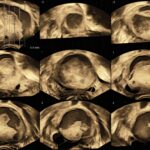

Sistema ecografico per ostetricia, ginecologia e fertilità

VOLUSON S8 con Touch panel

- 3D Uterine Trace

- Immagini veloci chiare e uniformi

- Dettaglio e risoluzione di contrasto eccezionale

- Visualizzazione dei piccoli vasi e dei bordi nel cuore fetale con RadiantFlowTM

- HDlive: tecnologia di rendering 3D/4D di Voluson che trasforma i dati ecografici in immagini più realistiche con profondità, illuminazione e texture migliorate